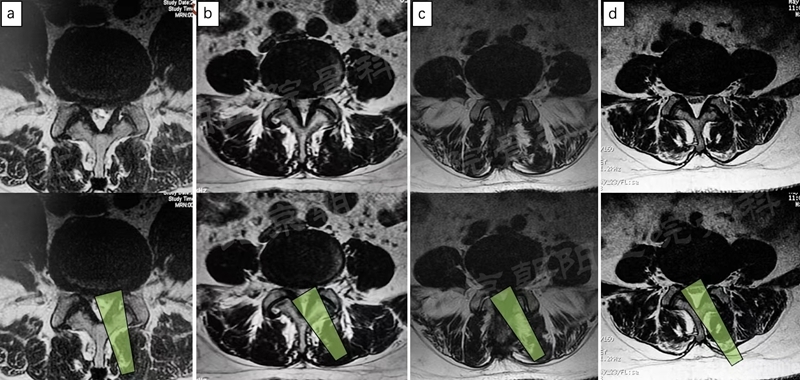

在经历15例UBE减压手术的学习曲线后,本团队进行了UBE腰椎减压融合术:#16例UBE,L4/5 LSS。

UBE-LIF手术步骤大致按常规开放手术:

1、显露L4椎板下缘-L4/5关节突-L5椎板上缘;

2、Kerrison钳减压L4下关节突(全部去除)-L5椎板上缘-L5上关节内侧缘(尽量靠外)-黄韧带整体切除;

3、硬膜外止血,显露椎间盘,确定椎间隙位置和方向;

4、椎间隙处理:骨刀,髓核钳,终板刮刀,Kerrison钳,电凝,+耐心;

5、自体骨+同种异体骨植骨;

6、可撑开融合器植入(透视定位);

7、检查遗漏的骨块,彻底清除神经周围的致压物;

8、必要时做对侧黄韧带减压;

9、经皮植入椎弓根螺钉,加压固定。

术前MRI和术中定位

椎间隙处理

植入可撑开Cage